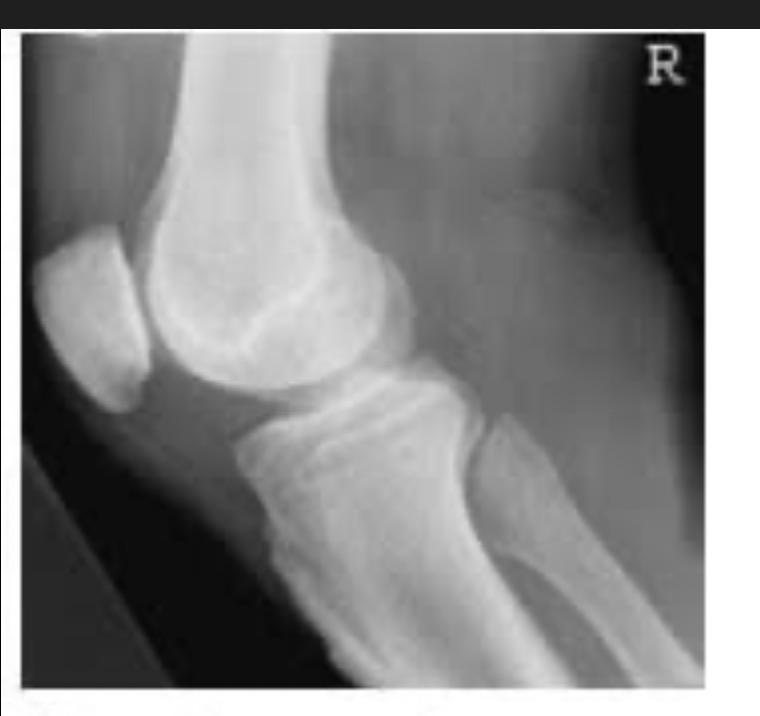

Name the projection.

Should it be repeated, if so why?

Lateral Knee

Yes. Patient is not in true lateral.

Fibular head and tibia are not superimposed.

Femoral condyles not superimposed

Label the image

A) Femur

B) Patella

C) Intercondylar eminence

D) Tibia

E) Fibular shaft

F) Fibular neck

G) Fibular head

H) Femorotibial joint

I) Femoral condyles